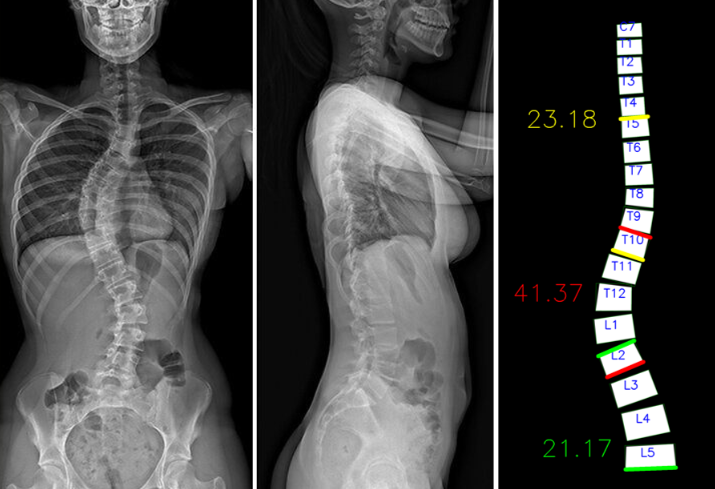

- Automatic and semi-automatic Cobb angle measurement tool for spinal X-ray images (coronal & sagittal planes), implemented with OpenCV + NumPy.

- Project worked at Shenzhen Institutes of Advanced Technology, Chinese Academy of Sciences.